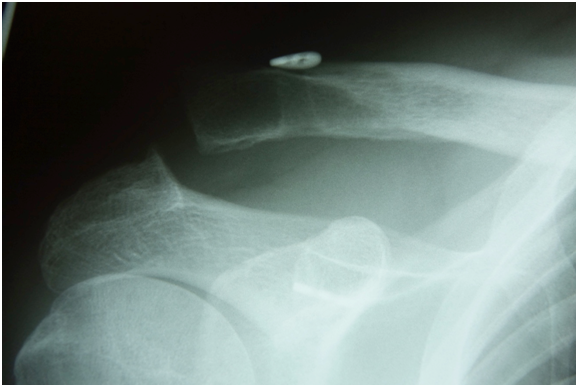

Twenty-one of 25 patients had an anatomic reduction of their AC joint (Figure 2). Four were reduced to a near-anatomic (within 2mm) reduction. There were no intraoperative complications. There were no fractures of the coracoid or the clavicle.

Figure 2 Intra-operative radiograph of anatomic reduction of AC separation with the Tight-rope device (Arthrex, Naples, FL).